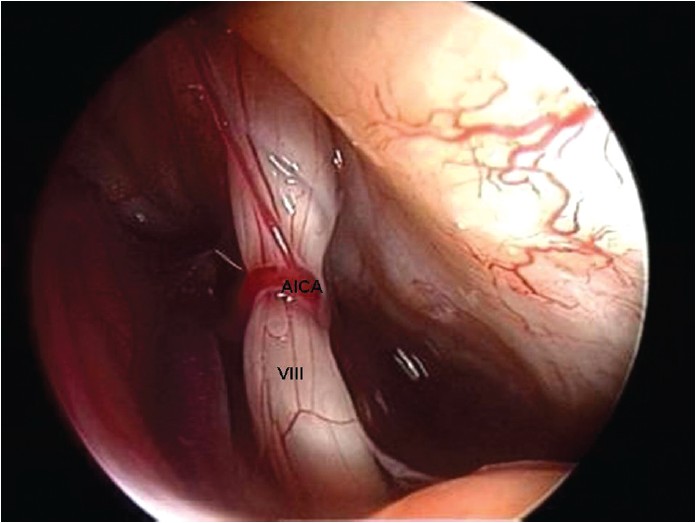

Vestibül-koklear sinir için, bir nörovasküler temasın tek varlığı tek başına yeterli değildir; bir veya daha fazla ortak kriterin varlığı olması, teşhisi için gereklidir. Bir başka önemli bulgu, vestibülokoklear sinirde bir baskı izinin varlığı ve siniri çevreleyen vasküler damarın loop'u ile sinir çapının azalmasıdır. Son olarak interakustik kanalda bir arteriyel döngü varlığı olabilir. Kulak çınlamasına veya vertigoya neden olabilir. ( [Şekil 3] )

Bu sinir, iç kulağın denge kısmı ve işitme ile ilgili alanlarının siniridir. Bir kemik kanalda içinden geçer bu inter akustik kanal adı verilen yapı içinde aynı anda damarlar, yüz siniri (7. sinir) ve vestibulokoklear sinir (8. sinir – işitme denge siniri) bulunur. Vestibüler paroksisminin sekizinci kraniyal sinirin (vestibüloklear -işitme denge siniri ) bir mikro arter tarafından sıkışması nedeniyle oluştuğu varsayılmaktadır.

Cerrahi: Tıbbi tedavi istenen sonuca ulaşılamamış ise ameliyat yapılabilir. Vestibüler siniri sıkıştıran bir vasküler lup (katlanma – sıkışma yapan kısım) mikrovasküler dekompresyon adı verilen işlem ile sinire yansıyan baskı ortadan kaldırılabilir. Uzman ellerde minimal morbidite ile endoskopik olarak yapılabilir.